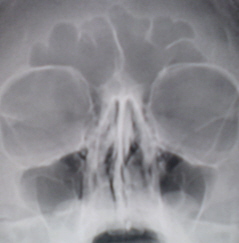

На иллюстрации 9. С обеих сторон пристеночно в гайморовых полостях определяется снижение прозрачности значительной ширины, что скиалогически создает эффект уменьшения объёма пазух.